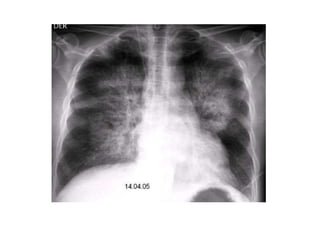

• #51 Paciente masculino de 63 años que refiere tos, disnea y dolor torácico derecho de aproximadamente siete días de evolución. El examen físico revela hipo ventilación en hemitorax derecho. Como dato positivo de laboratorio presenta VSG aumentada. Se solicita inicialmente una radiografía de tórax frente en la cual se observa, radioopacidad basal derecha con broncograma aéreo que borra el seno costofrénico homolateral. Engrosamiento pleural difuso que impresiona comprometer pleura mediastínica. Dados los hallazgos en la radiografía se decide ampliar el diagnostico solicitándole una TAC de tórax con contraste endovenoso en la cual se observa engrosamiento circunferencial pleural de hemitorax derecho. Atelectasia de segmentos inferiores con broncograma aéreo. Pequeña área líquida tabicada. Adenomegalias mediastinales en región prevascular, pretraqueal retrocavo y ventana aortopulmonar. Caja torácica sin alteraciones tomográficamente demostrables. Estructura y densitometría osteoarticular de l raquis dorsal normal. DIAGNOSTICOS DIFERENCIALES: • Engrosamiento pleural: Derrame organizado, hemotórax, piotorax, cirugía previa, radioterapia, exposición al Asbesto. • Tumores Benignos: lipomas, tumores fibrosos, esplenosis torácica. • Tumores malignos: MTTS de pulmón, mama, linfoma. • Mesotelioma maligno. DIAGNOSTICO DEFINITIVO: • MESOTELIOMA MALIGO